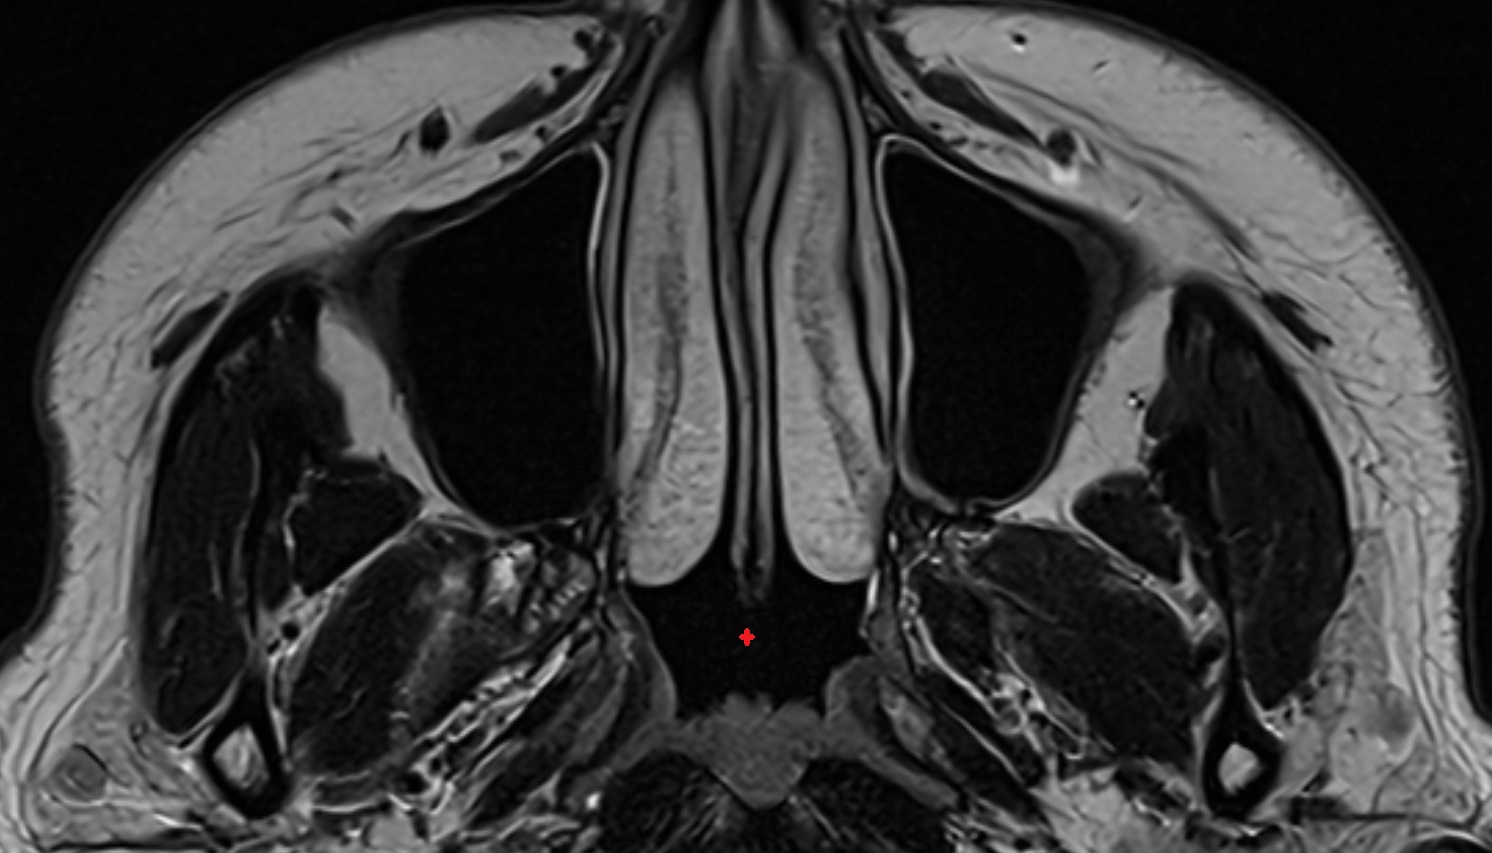

- Maxillary sinus

- Inferior nasal concha

- Middle nasal concha

- Nasal septum

- Superior nasal concha